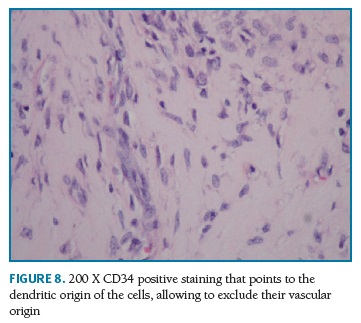

Definitive pathologic diagnosis of Pseudoangiomatous Stromal Hyperplasia (Fig. 4-5-6-7-8) was made on surgical specimen of mastectomy. The patient had regular follow-up at our department. Last visit was in May 2018, and no signs recurrence or contralateral breast cancer were diagnosed in those 11 years of follow-up.

Additionally, Samaila et al (2018)12 reports the case of a 34-year-old woman with a 2 year history of rapid progressive painless bilateral enlargement of the breasts. The examination revealed bilateral nontender giant breasts extending to the umbilical area with masses which were not attached to overlying skin and Grade 2 pressure ulcers on the lateral posterior breast aspects bilaterally. A bilateral mastectomy was performed and it revealed giant PASH which was confirmed by the positive immunohistochemical reactivity for CD34 and vimentin. No other breast pathologies were seen with extensive sectioning.

Similarly, the case reported by Dai et al (2014)16 presents a rare case of diffuse tumorous PASH involving bilateral breasts, clinically similar to a malignant lesion. The patient presented a one-year history of bilateral breast enlargement and asymmetry. Physical examination revealed multiple palpable nodule in bilateral breasts. Biopsy of the breast nodules demonstrated a diagnosis consistent with PASH. The stromal cells were positive, at the immunohistochemical staining, for estrogen receptor (ER) and progesterone receptor (PR) and negative for CD31, supporting the diagnosis of PASH. A bilateral mastectomy was performed, with immediate reconstruction.